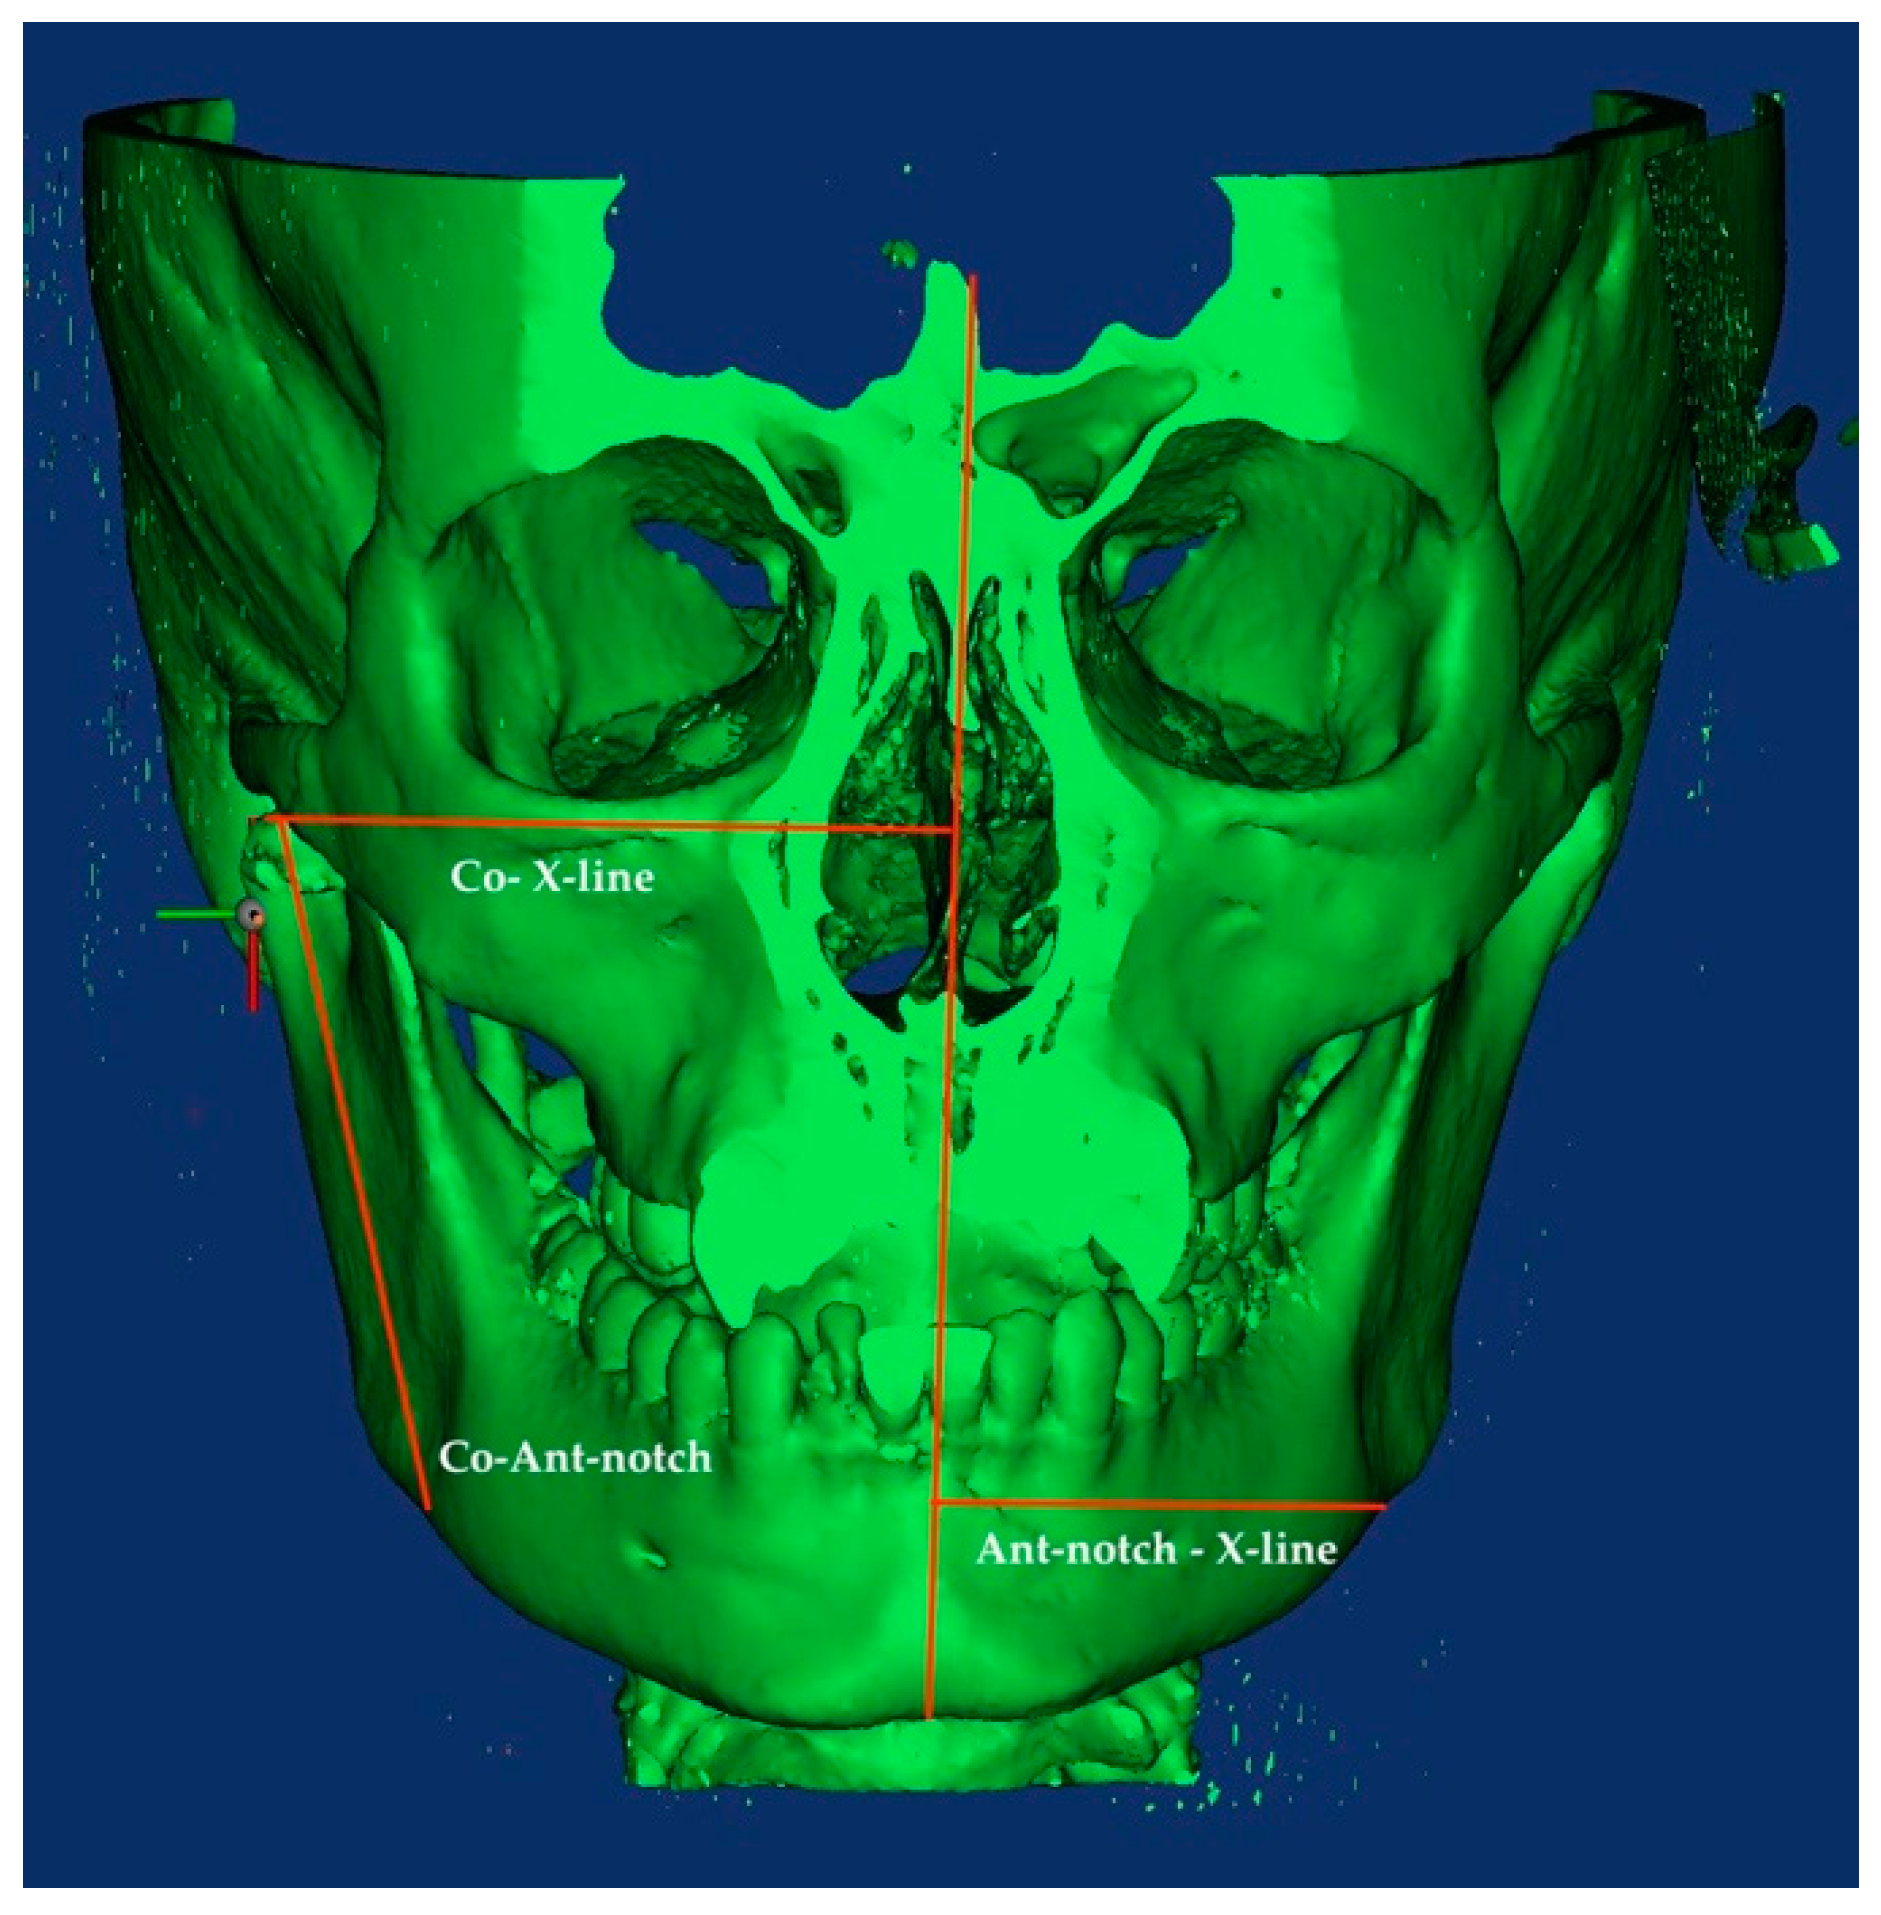

2.4.3. D Skeletal Asymmetry Assessment

- Condylion—X-Line distance: horizontal distance between the X-Line and the upper point of the condylar head;

- Antegonial notch—X-Line distance: horizontal distance between the Antegonial notch and the X-Line;

- Antegonial-notch—Condylion distance: vertical distance between the upper point of the condylar head and the antegonial notch.